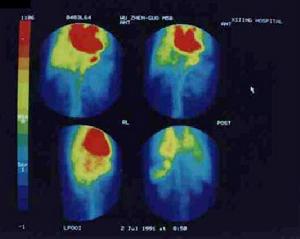

(6)放射性核素顯像:放射性核素顯像曾是肝癌診斷的重要手段,但由於核素顯像的解析度低,隨著B超CTMRI等顯像技術的發展,核素顯像檢查的臨床套用價值有所下降。近年由於單光子發射計算機斷層顯像(SPECT)和電子計算機斷層(PET)的套用以及單克隆抗體作放射免疫顯像等,又重新得到重視其檢出低限約為2cm。此方法對肝癌與血管瘤的鑑別有較大幫助。

5.放射性核素顯影 核素掃描診斷的特點是方法簡單,無創傷但只能檢查有無占位性病變不能確定病變的性質只能顯示≥3cm的肝癌,而瀰漫型顯示差對巨塊型大肝癌的診斷率為92.3%。99mTc-PMT(99mTc吡多醛五甲基色氨酸)為一理想的肝膽顯像劑肝膽通過時間短,肝癌、肝腺瘤內無膽管系統供膽汁排泄並與PMT有一定親和力故可在肝癌、肝腺瘤內濃聚停留較長時間,在延遲顯像(2~5h)時肝癌和肝腺瘤組織中的99mTc-PMT仍滯留,而周圍肝實質細胞中已排空使癌或腺瘤內的放射性遠高於正常肝組織而出現“熱區”故臨床套用於肝癌的定性定位診斷。如用於AFP陰性肝癌的定性診斷鑑別原發性和繼發性肝癌肝外轉移灶的診斷和肝腺瘤的診斷原發性肝癌的血供豐富功能活躍,除因中心壞死或個別血供不佳者,肝血池顯像見原缺損區內出現放射性充填現象轉移性肝癌病灶缺乏血供故血池掃描無充填現象。肝血管瘤表現原缺損區過度充填特徵。原發性肝癌的99mTc-PMT血池延遲相陽性率>90%特異甚強而轉移性肝癌膽管細胞癌、海綿狀血管瘤則為陰性具鑑別意義